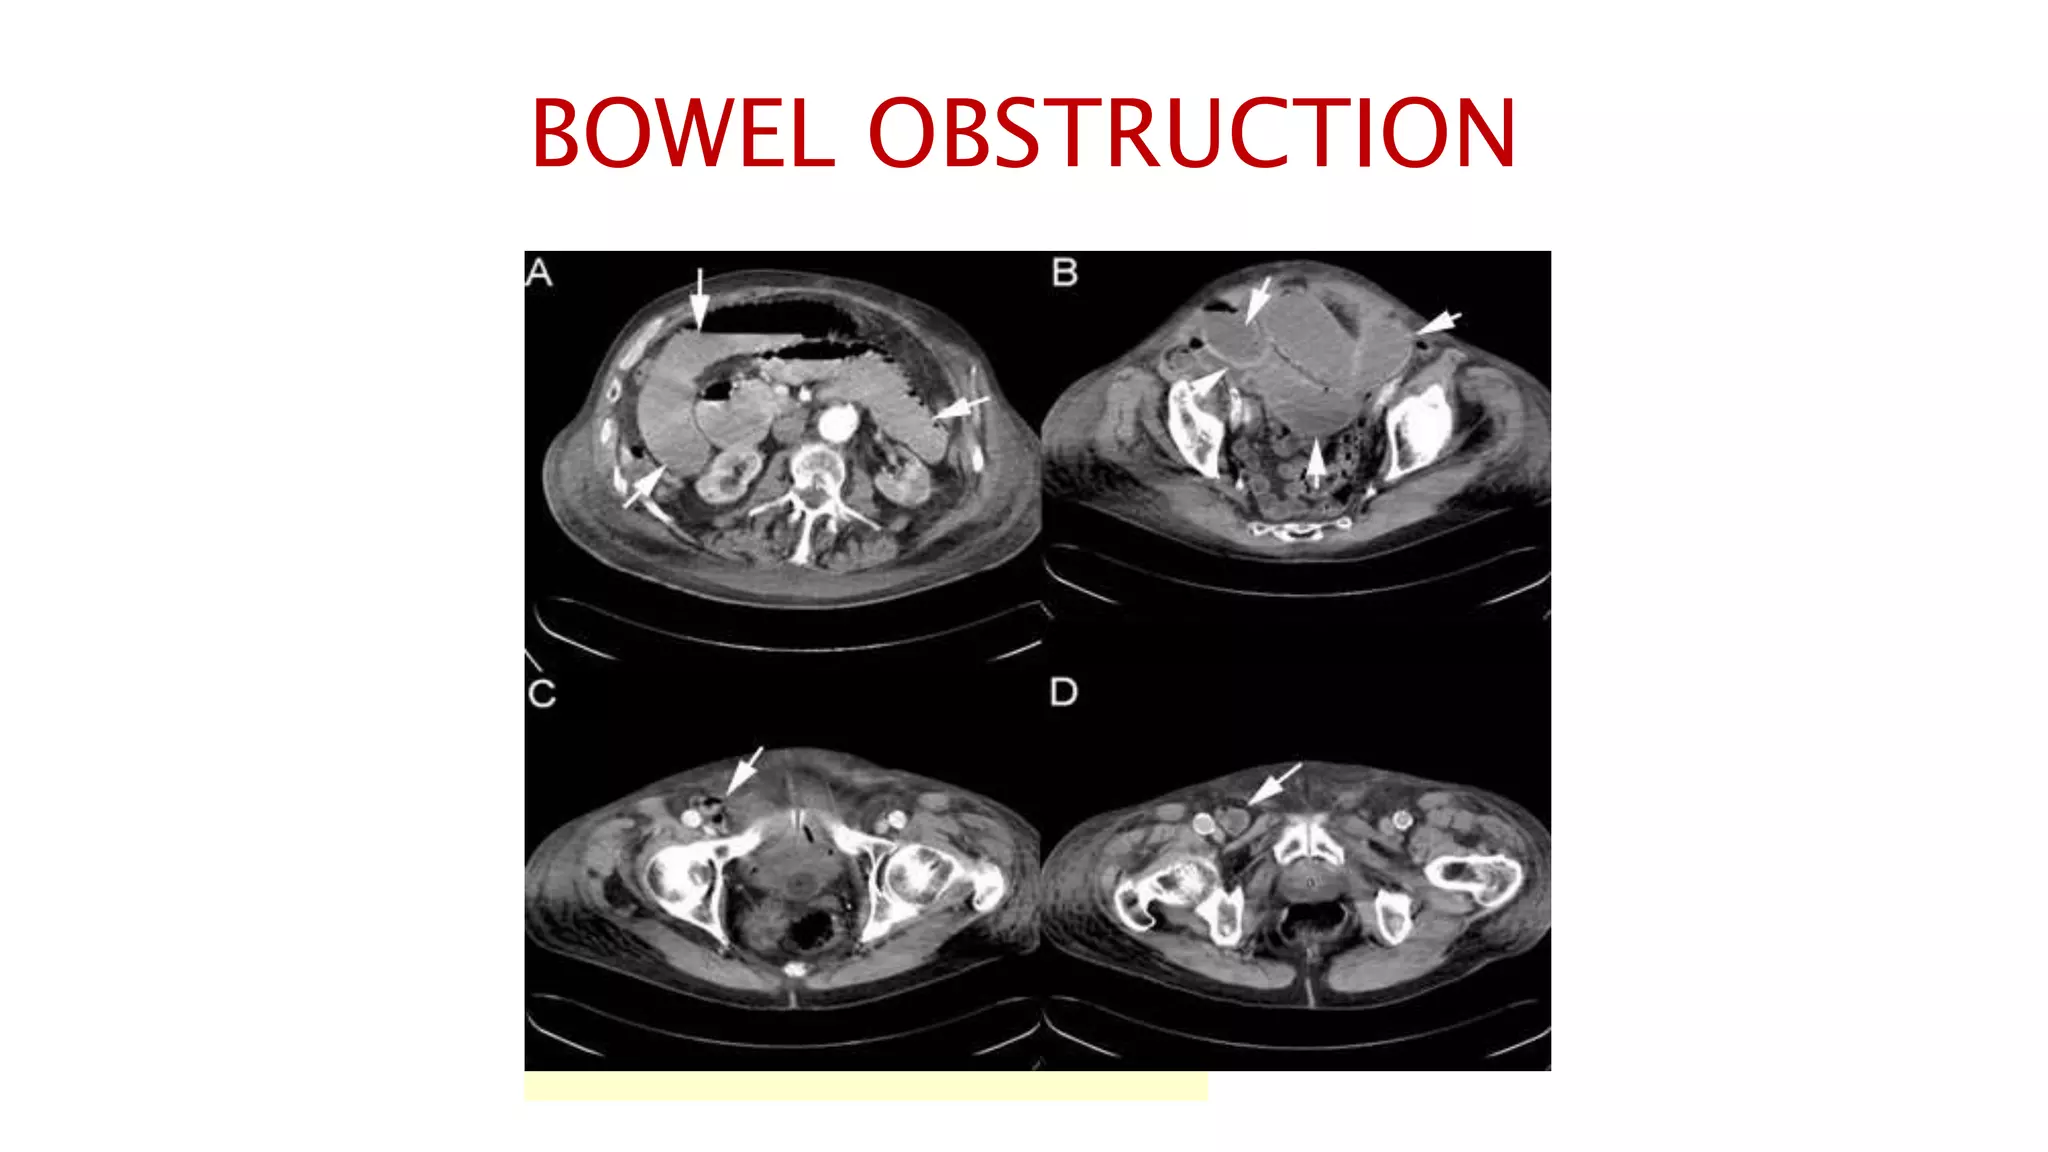

BOWEL OBSTRUCTION